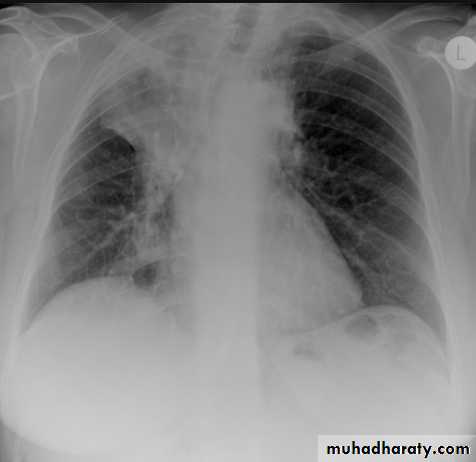

Left upper lobe collapse has distinctive features but can be challenging to identify on chest radiographs by the uninitiated.

Radiographic features

The left upper lobe collapses anteriorly becoming a thin sheet of tissue apposed to the anterior chest wall, and appears as a hazy or veiling opacity extending out from the hilum and fading out inferiorly . It thus reverses the normal slight increase in radiographic density seen as you move down the lung (due to increased thickness of the chest soft tissues).

Parts of the normal cardiomediastinal contour may also be obliterated where the left upper lobe, particularly the lingula abut the left heart border. The anterior parts of the aortic arch are also often obliterated from view.

In some cases the hyperexpanded superior segment of the left lower lobe insinuates itself between the left upper lobe and the superior mediastinum, sharply silhouetting the aortic arch and resulting in a lucency medially. This is known as the HYPERLINK "http://radiopaedia.org/articles/luftsichel-sign" luftsichel sign.

The left hilum is also drawn upwards, resulting in an almost horizontal course of the left main bronchus and vertical course of the left lower lobe bronchus.

Non-specific signs indicating left sided atelectasis will also be present, including:

elevation of the hemidiaphragm

'peaked' or 'tented' hemidiaphragm: HYPERLINK "http://radiopaedia.org/articles/juxtaphrenic-peak-sign" juxtaphrenic peak sign

crowding of the left sided ribs

shift of the mediastinum to the left

On lateral projections the left lower lobe is hyperexpanded and the oblique fissure displaced anteriorly. There is associated increase in the retrosternal opacity.